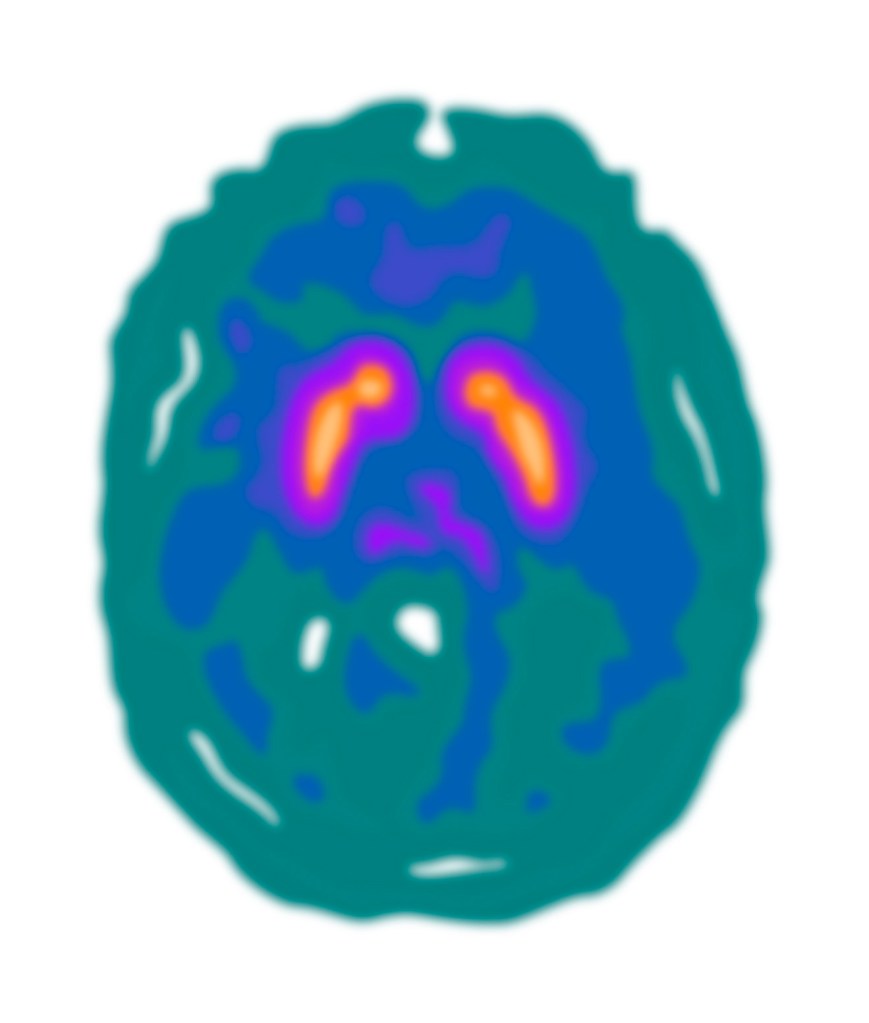

Gill experimented with drawing the rainbow colour-scheme and the blue-green colour scheme PET scans, as the red colour scheme is not as visually appealing and would not work as well with the existing illustrations. The scans will have to be placed on a black background (as in the header image of this post) to look their best, and to match how the scan results appear in the PET imaging software.

Gill then revised the text to even out the line lengths and adjust spacings. As the PET scans require a black background, Gill extended that down from the title bar. This black are does help to separate the first two sections of the text from the third section, although the layout will probably need more work. Gill added the blue-green PET scan illustrations, although the colours can be changed – it may be worth including some red to tie-in with the KCL logo and the elapsed time image. She also added the blue-green PET scan images to the screens in the radiographer illustration.